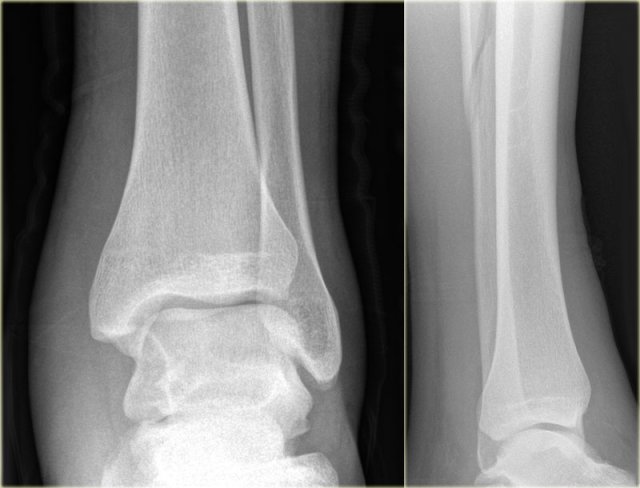

Weber C fracture - at least stage 3 Weber C fracture - at least stage 3

Here an example of a Weber C fracture with a proximal fibula fracture.

Notice that on the radiograph of the ankle no fracture is seen.

You might misdiagnose this as only some soft tissue swelling.

In fact this is an unstable ankle fracture, since there also must be a rupture of the medial collateral ligament (stage 1) , so the ring is broken in two places leading to instability.

According to Lauge Hansen we are probably dealing with:

1. Medial collateral band rupture

2. Rupture of the anterior syndesmosis

3. High fibula fracture

4. and possibly a rupture of the posterior syndesmosis